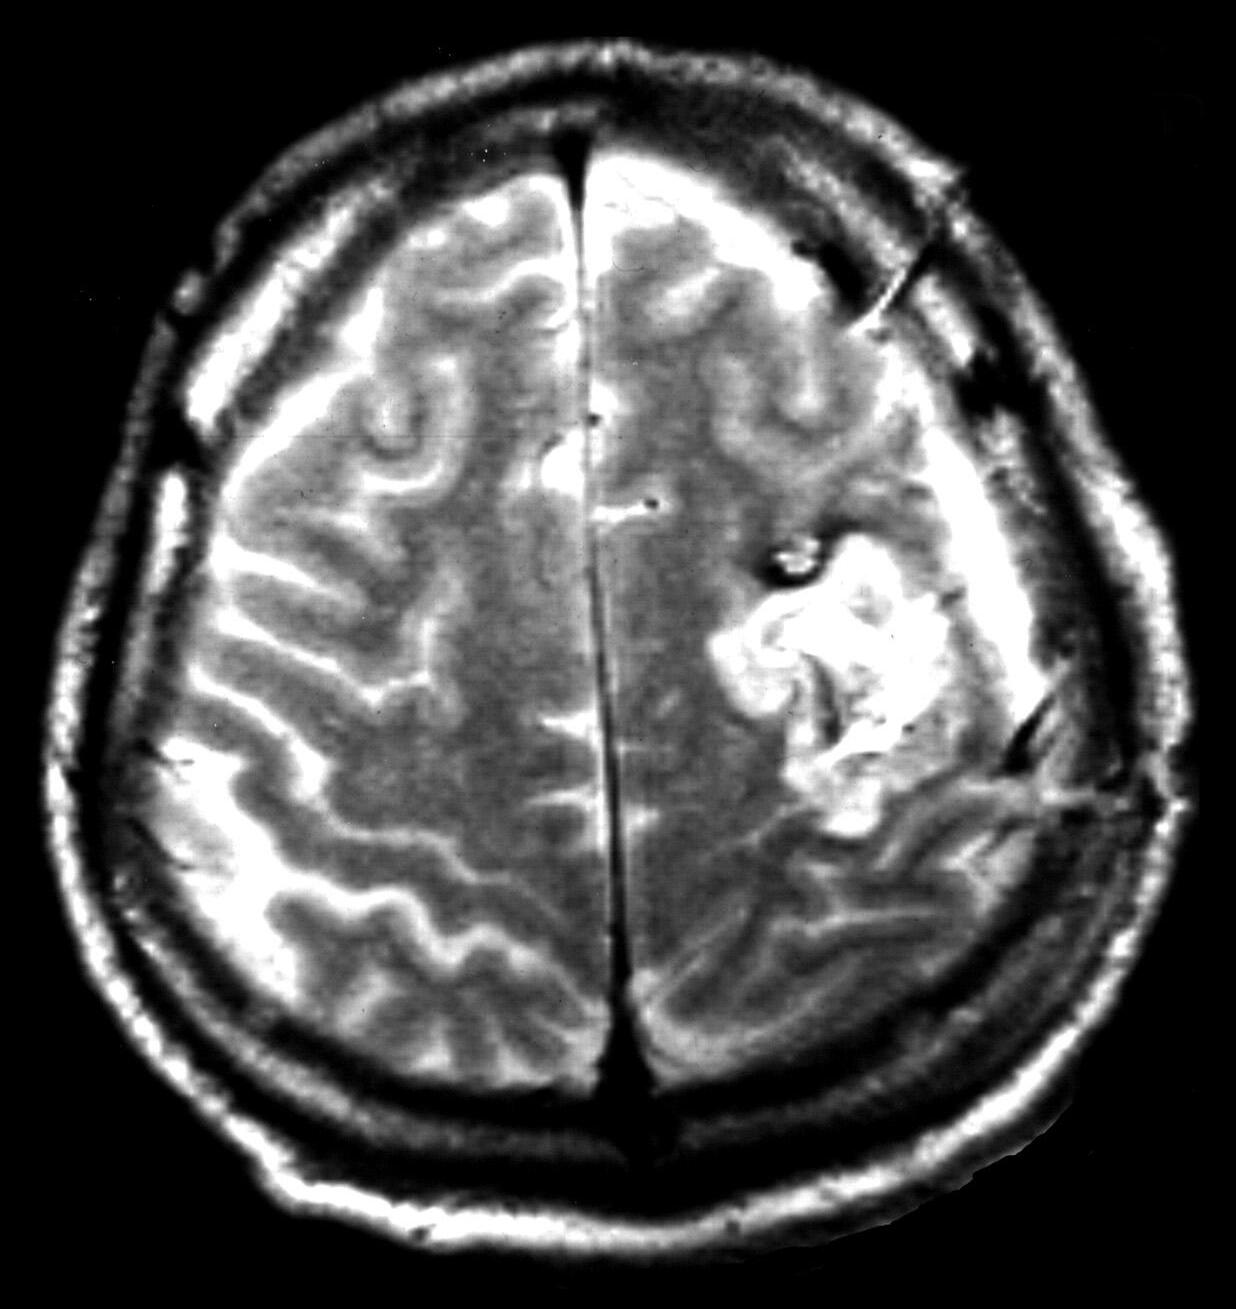

Obr.1.3 Chybnéurčenípolohyhemangiomuvzhledemksulcuscentralis

A: PředoperačníMRI:Frontálněvlevojuxtakortikálněložisko10×7mm. B: Operacebeznavigaceabezurčenízvratu fází.Připrvníoperacibylaprovedenapředsulcuscentralis,předv.precentralis,sulkotomieagyrotomie.Vhloubce3cm bylanalezenaširokážíla,jinakbylnáleznepřesvědčivý.Pooperacihemiparézavpravoaafázie.MRI:posteriorněodznáméhokavernomujsouprokrvácenépooperačnízměny.Podalšíoperacičástečnáapotřetíoperaciúplnáexstirpacekavernomu.Intracerebrálníhematom7×5cmfrontálněvlevo.Hemiplegievpravoaafázie.Dokladynejsouzpracovišťautorů.